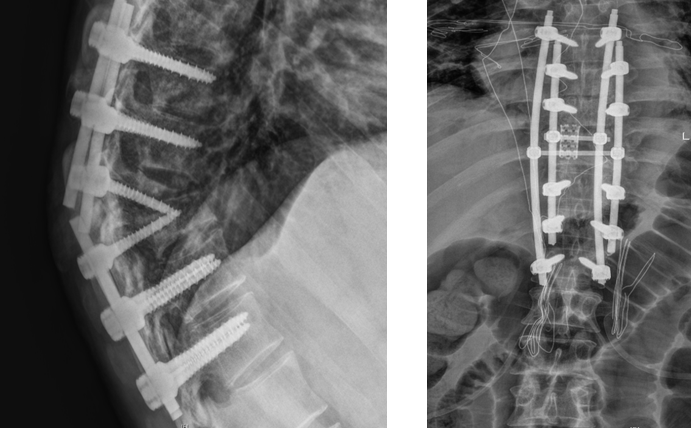

“前次手术部位已经改变了原有生理组织结构,再次‘翻修’,对术者的操作水平无疑是巨大挑战,且出血风险也会加大,加上患者存在耐药结核,意味着术后并发症发生率及感染风险更高。”曾浩介绍,经过反复探讨,最后决定为患者施行胸椎后路内固定装置取出、结核病灶清除、截骨矫形、钛网植骨融合、棒系统内固定术这一手术方案,并创新性地采用四重钉棒加固手术部位,并截除部分增生病骨,达到解除患者病痛,愈后稳固、美观的手术目的。

术前:内固定失效及耐药结核加剧身体畸形 术后:多重加固恢复正常脊柱曲线